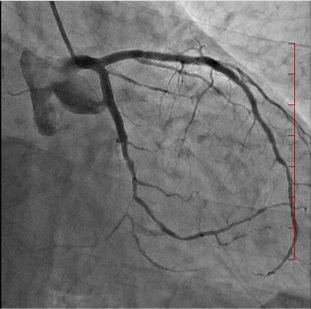

経皮的冠動脈形成術

経皮的冠動脈形成術とは、狭くなった、あるいは詰まった冠動脈(心臓の筋肉に血流を送る血管) に対し、カテーテルを用いる治療法の総称です。バルーンやステントを使用して冠動脈を広げる治療です。

| 治療前 | ステント留置中 | 治療後 |